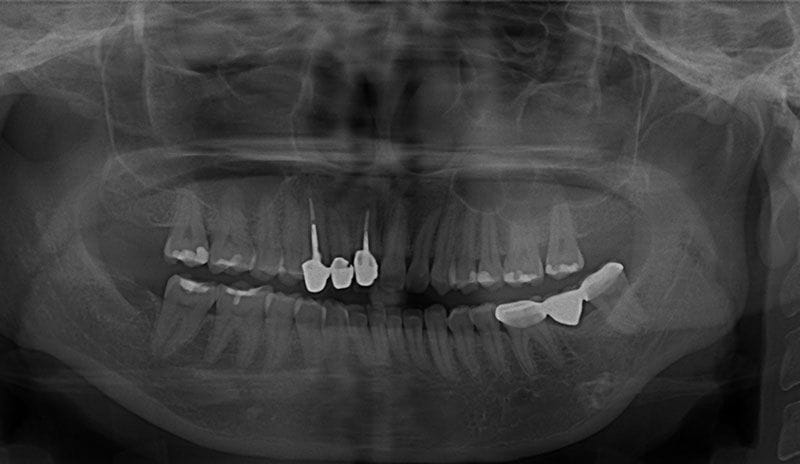

術前X光片

術後X光片